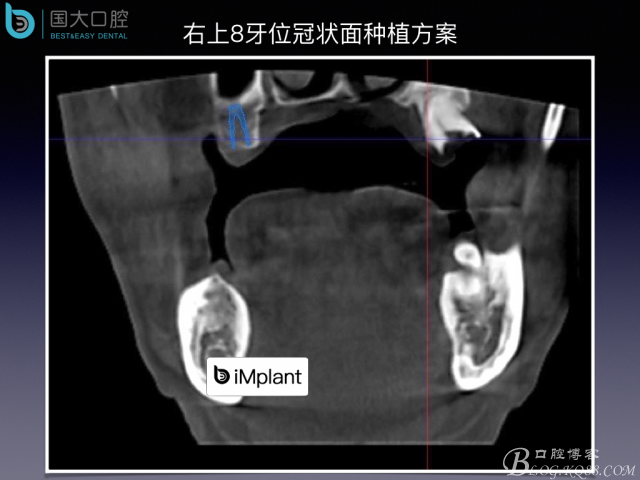

上頜竇底區(qū)域嚴(yán)重骨吸收的臨床種植案例

來(lái)源于國(guó)大口腔 邵現(xiàn)紅醫(yī)生發(fā)表的博文